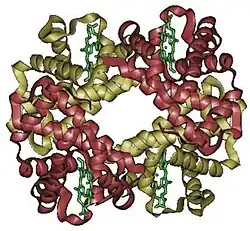

Hemoglobin G, Hemoglobin G-Philadelphia, or hbG, is a mutation of the cells that oxygenate blood. The G-Philadelphia variant is most commonly found in African Americans, with carriers being every 1 in 5,000.[1] The trait is normal-functioning and has no known negative effects.[2]

Schwartz et al confirmed that Hemoglobin G is a normal mutation of the combination of S and A alleles, which is reflected in the chart below.[2]